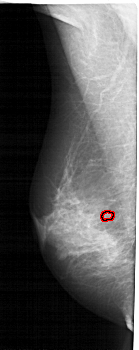

A_1929_1.LEFT_CC

LEFT_CC LINES 5086 PIXELS_PER_LINE 1936 BITS_PER_PIXEL 12 RESOLUTION 43.5 OVERLAY

FILE: A_1929_1.LEFT_CC.OVERLAY

TOTAL_ABNORMALITIES 1

ABNORMALITY 1

LESION_TYPE CALCIFICATION TYPE AMORPHOUS DISTRIBUTION CLUSTERED

ASSESSMENT 4

SUBTLETY 2

PATHOLOGY MALIGNANT

TOTAL_OUTLINES 1

BOUNDARY